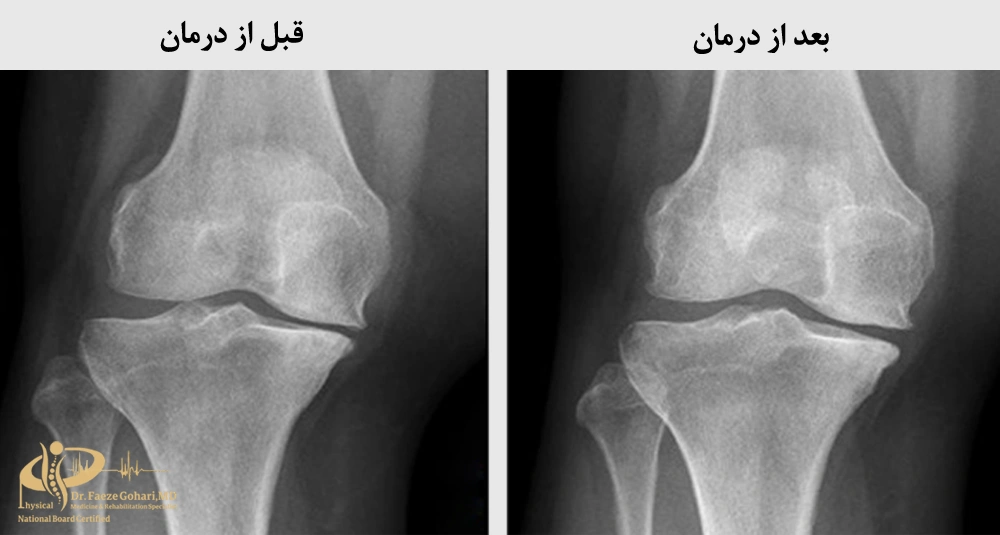

اوزون تراپی درمان قطعی آرتروز نیست، زیرا نمیتواند غضروف ازبینرفته را بازسازی کند، اما با کاهش التهاب، تسکین درد و بهبود جریان خون، به بهترشدن وضعیت مفصل کمک میکند. مزایای اوزون تراپی شامل کاهش ناراحتی، بهبود حرکت زانو و کند کردن تخریب غضروف است.

آینده درمان

بیماران مبتلا به آرتروز زانو در مراحل 1 و 2، به طور متوسط حدود 50 درصد بهبود در توانایی حرکت و کاهش درد را تجربه میکنند (منبع). بسیاری از بیماران پس از بهبود علائم، میتوانند به فعالیتهای روزمره مانند پیادهروی، رانندگی، و حتی ورزشهای سبک بازگردند. با این حال، چون آرتروز یک بیماری پیشرونده است، احتمال بازگشت تدریجی علائم در طول زمان وجود دارد. بنابراین، پایش مداوم وضعیت مفصل، سبک زندگی فعال اما محافظهکارانه، و پیروی از توصیههای پزشک نقش مهمی در حفظ اثربخشی دارند.